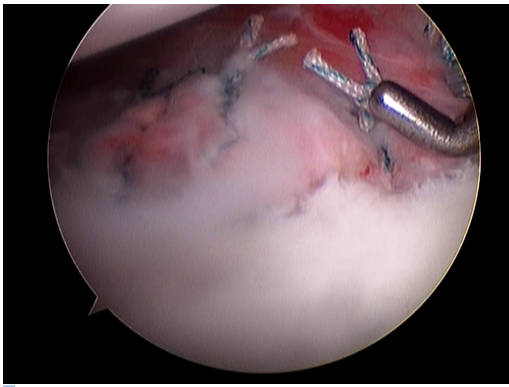

만성 불안정성의 경우 그 정도 및 종류에 따라 치료의 방법이 달라질 수 있으며 다방향 불안정성의 경우 혹은 전방 불안정성의 경우에도 그 정도가 심하지 않은 경우에는 물리 치료 등을 이용한 보존적 치료를 시행하여 볼 수 있으나, 반복적인 견관절의 전방 탈구 등이 지속될 때에는 수술적 치료가 필요합니다.수술적 치료의 방법은 관절이 탈구될 때 발생한 관절와순을 봉합하는 수술을 시행할 수 있으며 (일명 “방카르트수술”) 과거에는 관절을 열어 노출 시킨 후에 봉합하는 방법을 많이 이용하였으나 현재는 대부분 관절경을 이용하여 복원술을 시행하며 이로 인해 회복이 빠르고 수술 시 발생할 수 있는 관절 손상의 가능성이 줄었습니다. 골결손이 심한 경우에는 이에 대해 골이식 등의 치료법을 이용할 수 있습니다.